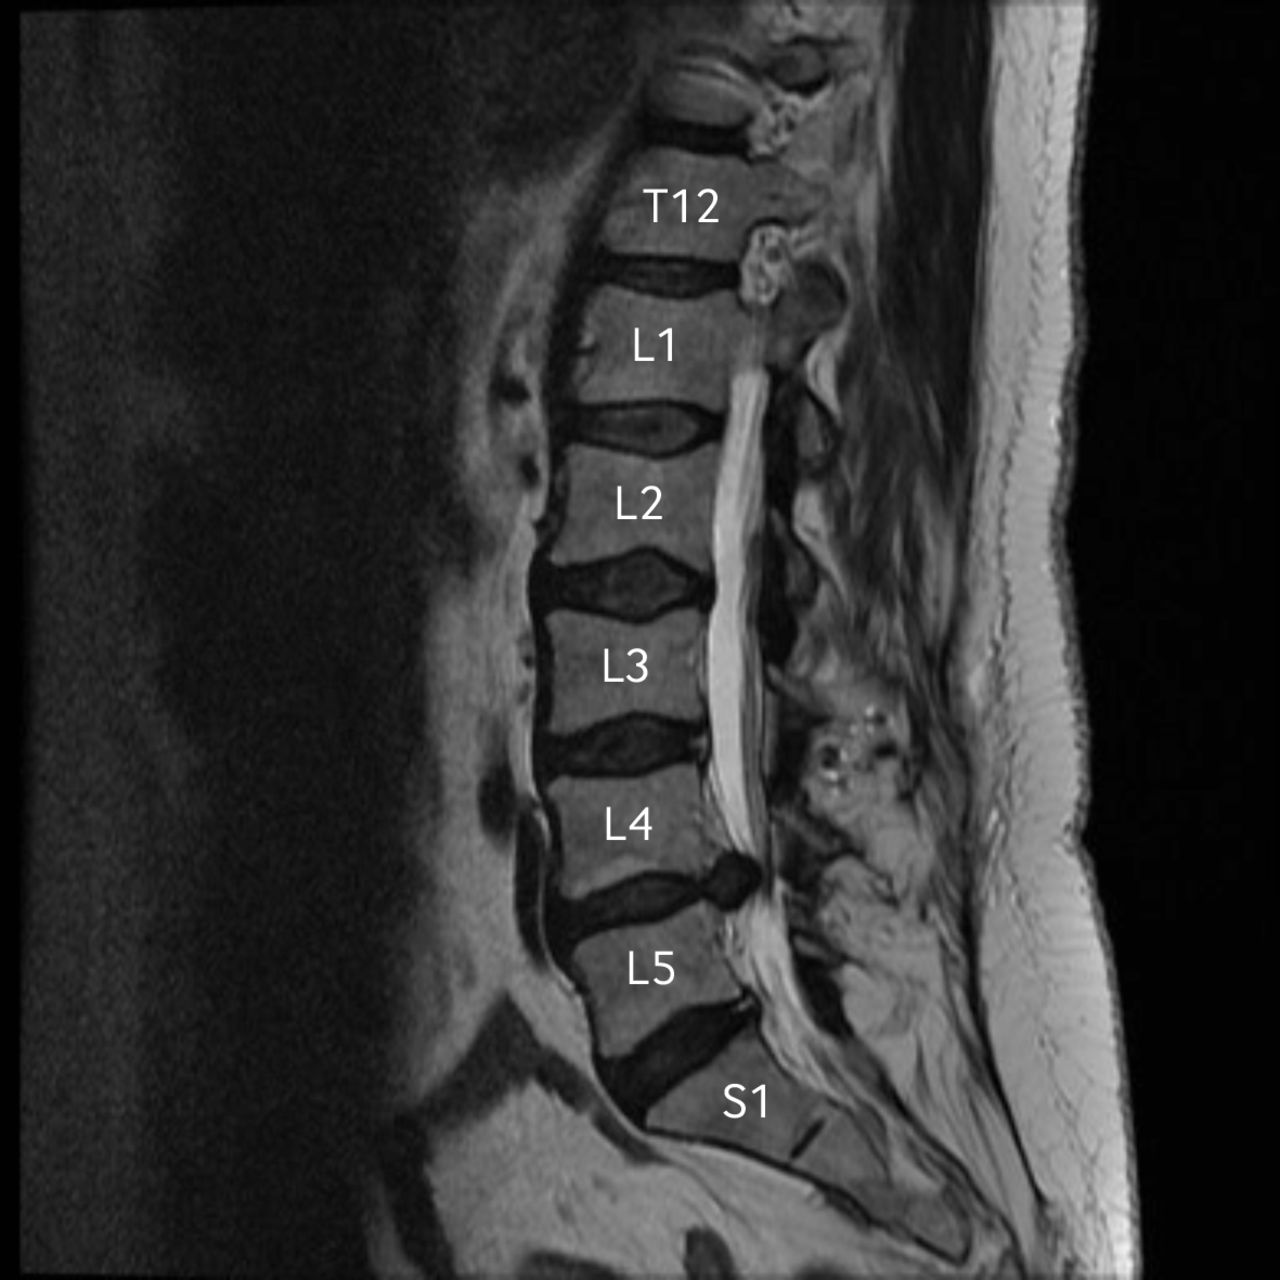

My threshold for pain is very high. I was told by my doctors the level of pain I am capable of tolerating without medication is beyond what the average person would be able to handle. With that being said, my back pain and associated leg pain was very difficult to treat. My first appointment for treatment was a visit to a spine and pain specialist. Based on my MRI results, I had two bulging discs, one of them leaking fluid and inflammation in my lower back at L4, L5, & S1. I was immediately scheduled for a set of three spinal injections consisting of two shots each visit, administered via X-ray, by an anesthesiologist over the following six weeks.

In early fall of last year, I had spinal fusion surgery on my L5-S1. My disc was removed , an artificial disc placed, along with a rod, and brackets to hold everything in place. Here I am 8 months later and still in pain. I recently visited my surgeon this week who was so caught up with other patients so my appointment was scheduled with his surgical assistant. After explaining to her I was randomly falling because of the pain in my back and leg were oftentimes unbearable, she stepped out of the room to consult with my surgeon to discuss if a CT-Scan or MRI would be best to determine if the nerves in my back were once again the cause of my pain.